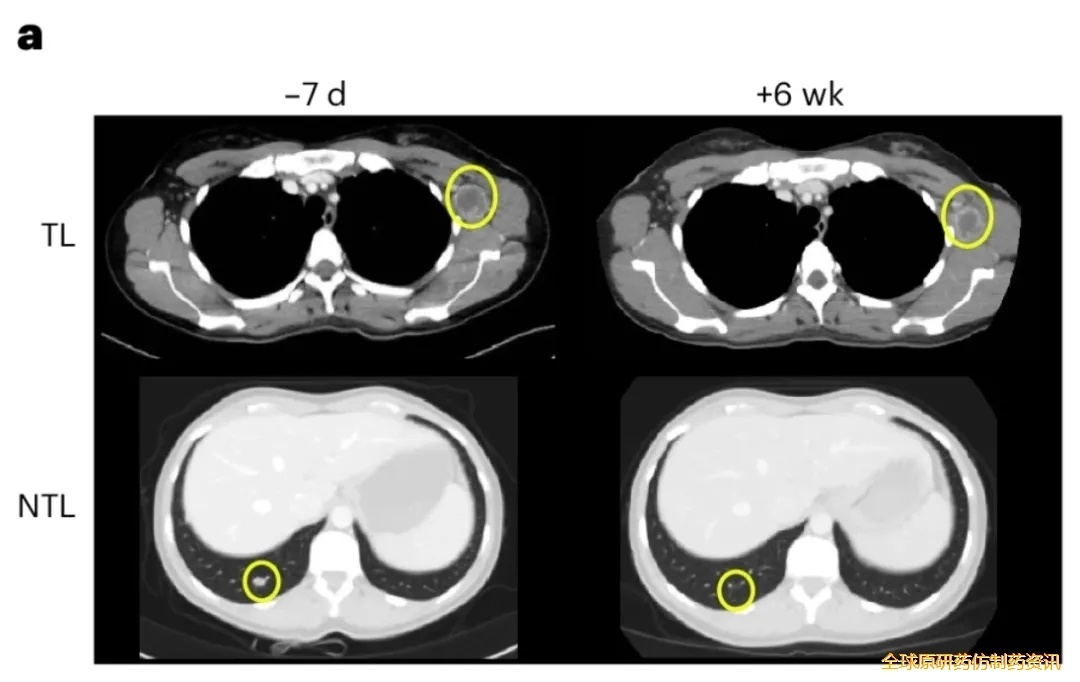

尤为值得关注的是NAC09号患者,其疗效最为突出:治疗6周后CT显示,左腋窝靶病变缩小20%,继发性腋窝淋巴结及毫米级肺转移灶等非靶病变显著缩小(详见下图)。

▼NAC09号患者治疗前后CT扫描对比

▲图源“Nature Medicine”,版权归原作者所有,如无意中侵犯了知识产权,请联系我们删除